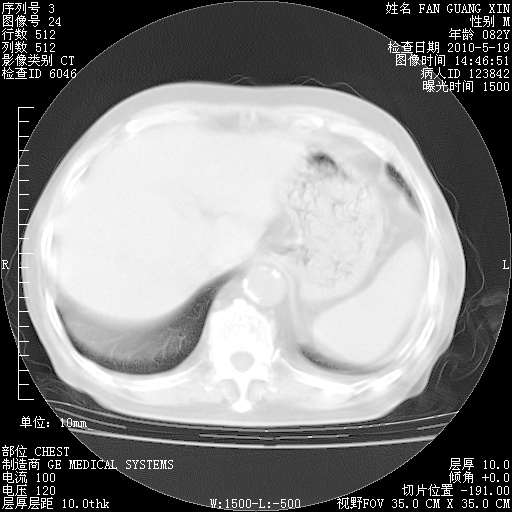

复查肺部CT,明显好转。为什么发热呢?

治疗3周后的肺部CT

治疗3周后的肺部CT纵隔窗